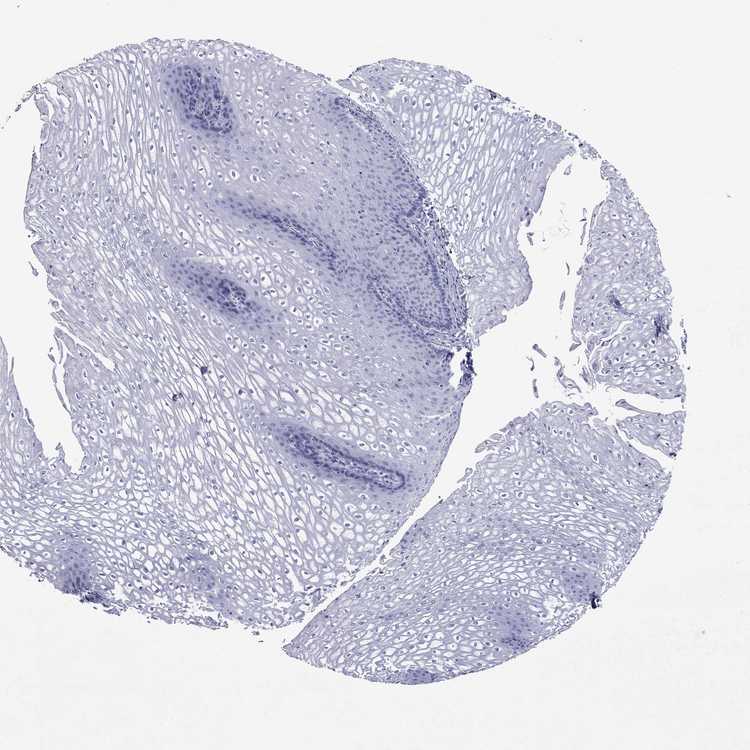

ESOPHAGUS - Antibody stainingi

Antibody staining in the annotated cell types in the current human tissue is reported as not detected, low, medium, or high, based on conventional immunohistochemistry profiling in selected tissues. This score is based on the combination of the staining intensity and fraction of stained cells.

Each image is clickable and will lead to virtual microscopy that enables deeper exploration of all samples and also displays staining intensity scores, fraction scores and subcellular localization as well as patient and tissue information for each sample.

Antibody HPA063181Antibody HPA065895

Squamous epithelial cells Not detectedNot detected